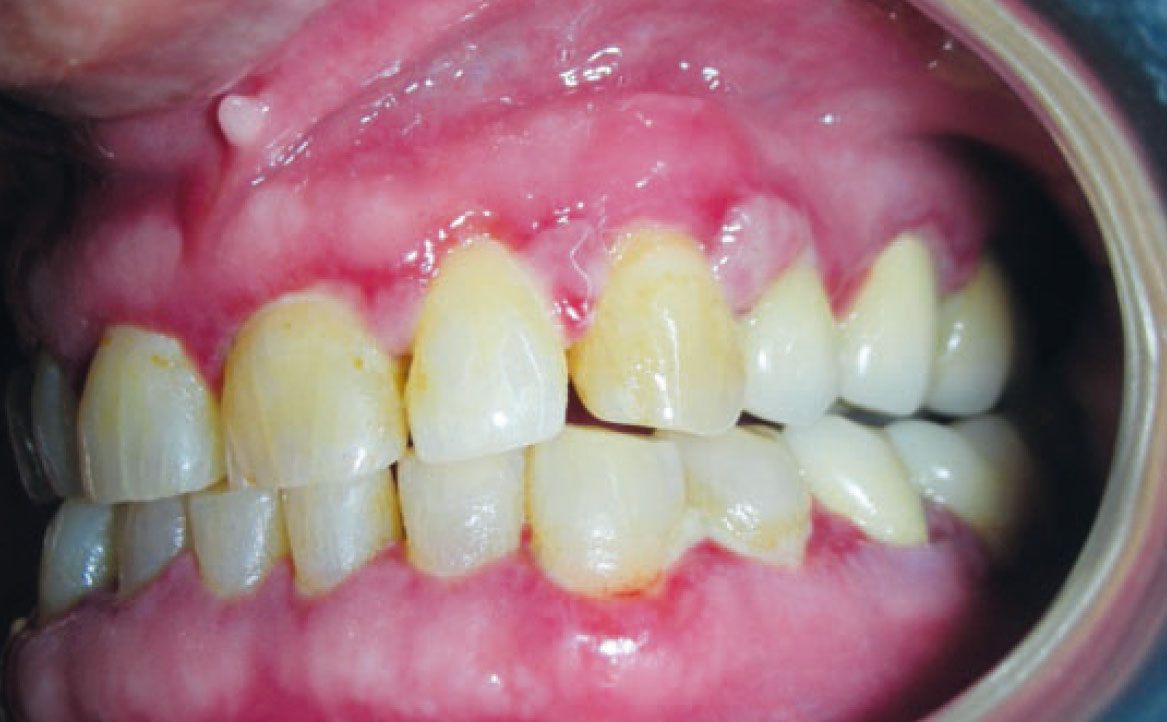

Il termine “aumento di volume gengivale farmaco-indotto” si riferisce comunemente a un effetto collaterale di alcuni farmaci utilizzati al di fuori della pratica odontoiatrica, per cui il tessuto gengivale non è il bersaglio previsto. Questi farmaci includono anticonvulsivanti come la fenitoina, che è la molecola più comunemente associata, immunosoppressori come la ciclosporina e calcio-antagonisti come la nifedipina (27) (fig. 10). Questa reazione avversa è principalmente legata a una predisposizione genetica e alla presenza di placca accompagnata da infiammazione gengivale, anche se i meccanismi esatti non sono ancora completamente compresi. La maggior parte dei farmaci responsabili agisce come inibitore dell’afflusso di ioni calcio. Questo porta a una diminuzione dell’assorbimento dell’acido folico nei fibroblasti del tessuto gengivale, il quale è essenziale per il corretto funzionamento della matrice delle metallo-proteinasi e l’attivazione delle collagenasi. Senza questa normale degradazione del collagene, si verifica un accumulo nel tessuto connettivale (28). Il trattamento può essere conservativo o chirurgico, mirando a ottenere un risultato estetico soddisfacente e a ridurre al minimo il disagio e il dolore. Se possibile, la sostituzione del farmaco implicato può portare alla regressione dell’iperplasia, supportata da un adeguato controllo della placca. Altrimenti, la soluzione chirurgica può essere l’unica opzione.

Clinicamente, i pazienti presentano un aumento di volume gengivale con pseudotasche, abbondante accumulo placca e difficoltà durante le manovre d’igiene orale domiciliare. Tale condizione è aggravata dall’infiammazione gengivale, conseguente all’accumulo di placca e tartaro, pertanto, è essenziale educare correttamente i pazienti sui potenziali effetti collaterali prima di iniziare qualsiasi trattamento farmacologico, sottolineando l’importanza di una igiene orale appropriata.